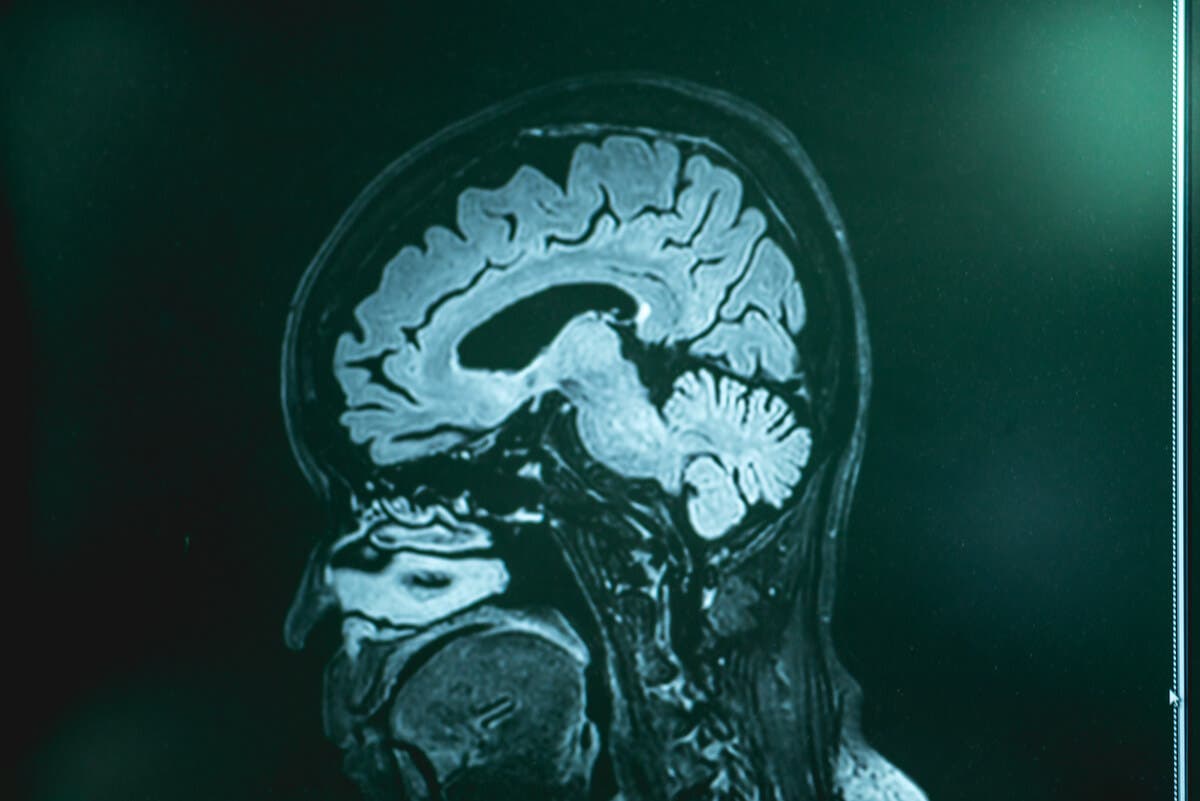

En av de mest brukte er magnetisk resonansavbildning. Dette bildet tillater detaljert observasjon av hjernevevet. Blod- og cerebrospinalvæskeprøver vil sannsynligvis også bli foreskrevet. For å oppnå sistnevnte bør det utføres en lumbalpunktur.